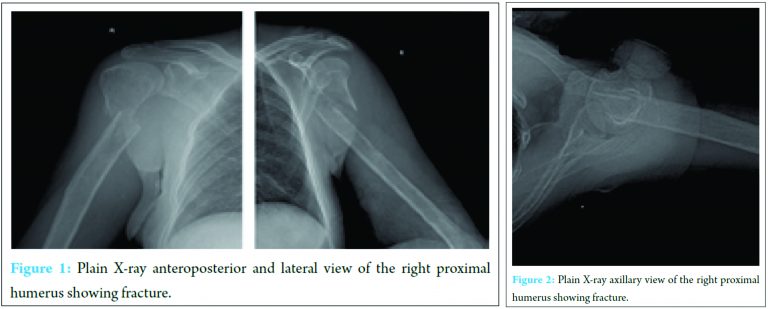

Systemic examination was normal. Neurologically, the patient was normal. Laboratory tests showed hemoglobin – 10 g/dl, total leukocyte count – 9500/cumm, neutrophils – 65%, lymphocytes – 30%, erythrocyte sedimentation rate (ESR) was raised – 40 mm/h. Plain radiograph (Fig. 1 and 2) followed by MRI (Fig. 3 and 4) of the right shoulder with humerus showed transverse fracture of proximal shaft of the right humerus, 5 cm distal to surgical neck. Articular surface was not involved.